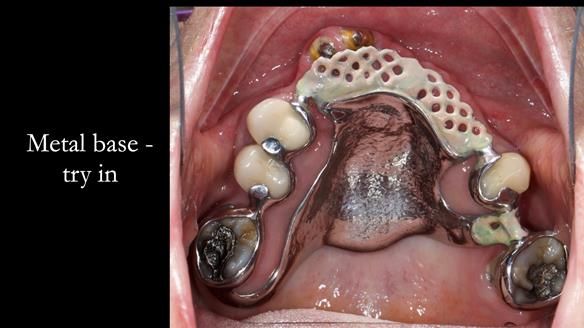

- Upper and lower metal based RPDs, poorly fitting, worn occlusal surface, reverse curve aesthetics, lacking support

- New metal based upper and lower RPDs of Scandinavian design for improved, periodontal health, function and appearance.

The clinical situation and treatment process is shown in detail below with photographs. I provided the clinical work. Rowan Garstang provided the technical work.